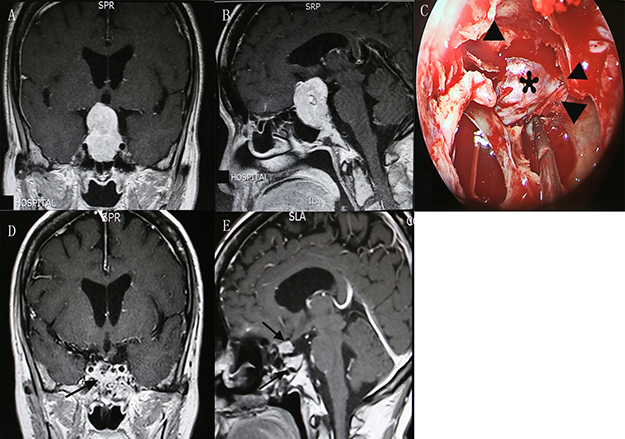

A 63-year-old female was admitted into our department with decreased visual acuity and bitemporal hemianopsia for 36 months. She also complained headache, impaired memory and unstable gait for 1 month. Preoperative magnetic resonance imaging (MRI) indicated a giant pituitary adenoma extending to suprasellar region and causing obstructive hydrocephalus (Figure 1A, 1B). Preoperative EVD was performed to relieve the hydrocephalus. Endoscopic transsphenoidal resection of the tumor was conducted under direct visualization (Figure 1C). Postoperative MRI confirmed a small residual of the tumor (Figure 1D, 1E). The postoperative course was uneventful. She obtained partial recovery of visual defect (preoperative/postoperative VIS: 77/34) and significant improvement of other symptoms at follow-up.

Figure 1: Contrast-enhanced MRI demonstrated preoperative coronal. (A) and sagittal (B) views of a giant pituitary adenoma. The suprasellar adenoma (asterisk) was viewed under direct visualization after the opening of diaphragma sellae (triangle) from the endoscopy. (C) Postoperative coronal (D) and sagittal (E) views showed a small residual of tumor and fat graft (arrow) placed in the pituitary fossa. MRI, magnetic resonance imaging.